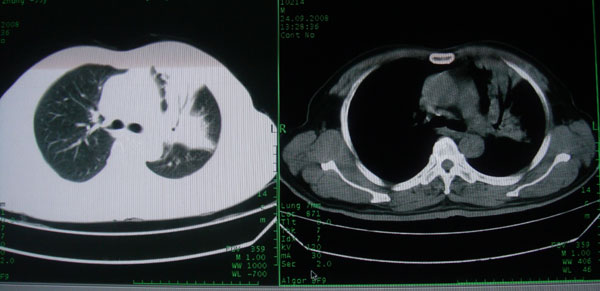

患者男性58岁因二周前起咳嗽,今天胸片示左上肺占位性病变行ct检查,无发热,无咯血痰.

左上肺感染性病变,结核伴空洞形成可能,左上肺膨胀不全

左肺上叶病灶,实变但见含气支气管、空洞但未见壁内结节及积液;

考虑:①感染性病变(包括特殊感染型肺tb)

②肿瘤性病变(考虑患者年龄比较大的关系/所以不排除)

初学者。。。左肺空洞性病变,并可见阻塞性肺不张改变,鉴于患者为老年男性,且临床症状仅有咳嗽,全身中毒症状不明显,所以我首先考虑为左肺癌性空洞并左侧肺门淋巴结转移伴左肺阻塞性肺不张。结核性空洞放于第二位考虑,可以进行相关实验室检查。希望能有病理结果,谢谢!!!!!

左肺上叶实变影,内见支气管充气征及空洞影,病人年龄较大,无发热及结核中毒症状,心影左移,未见纵隔淋巴结肿大;不知实验室检查结果如何?有否嗜酸细胞增多,有没有进行治疗?就目前资料首先考虑1.感染性病变,2.慢性嗜酸性肺炎?可结合实验室检查并短期治疗复查,肺癌不能排除。